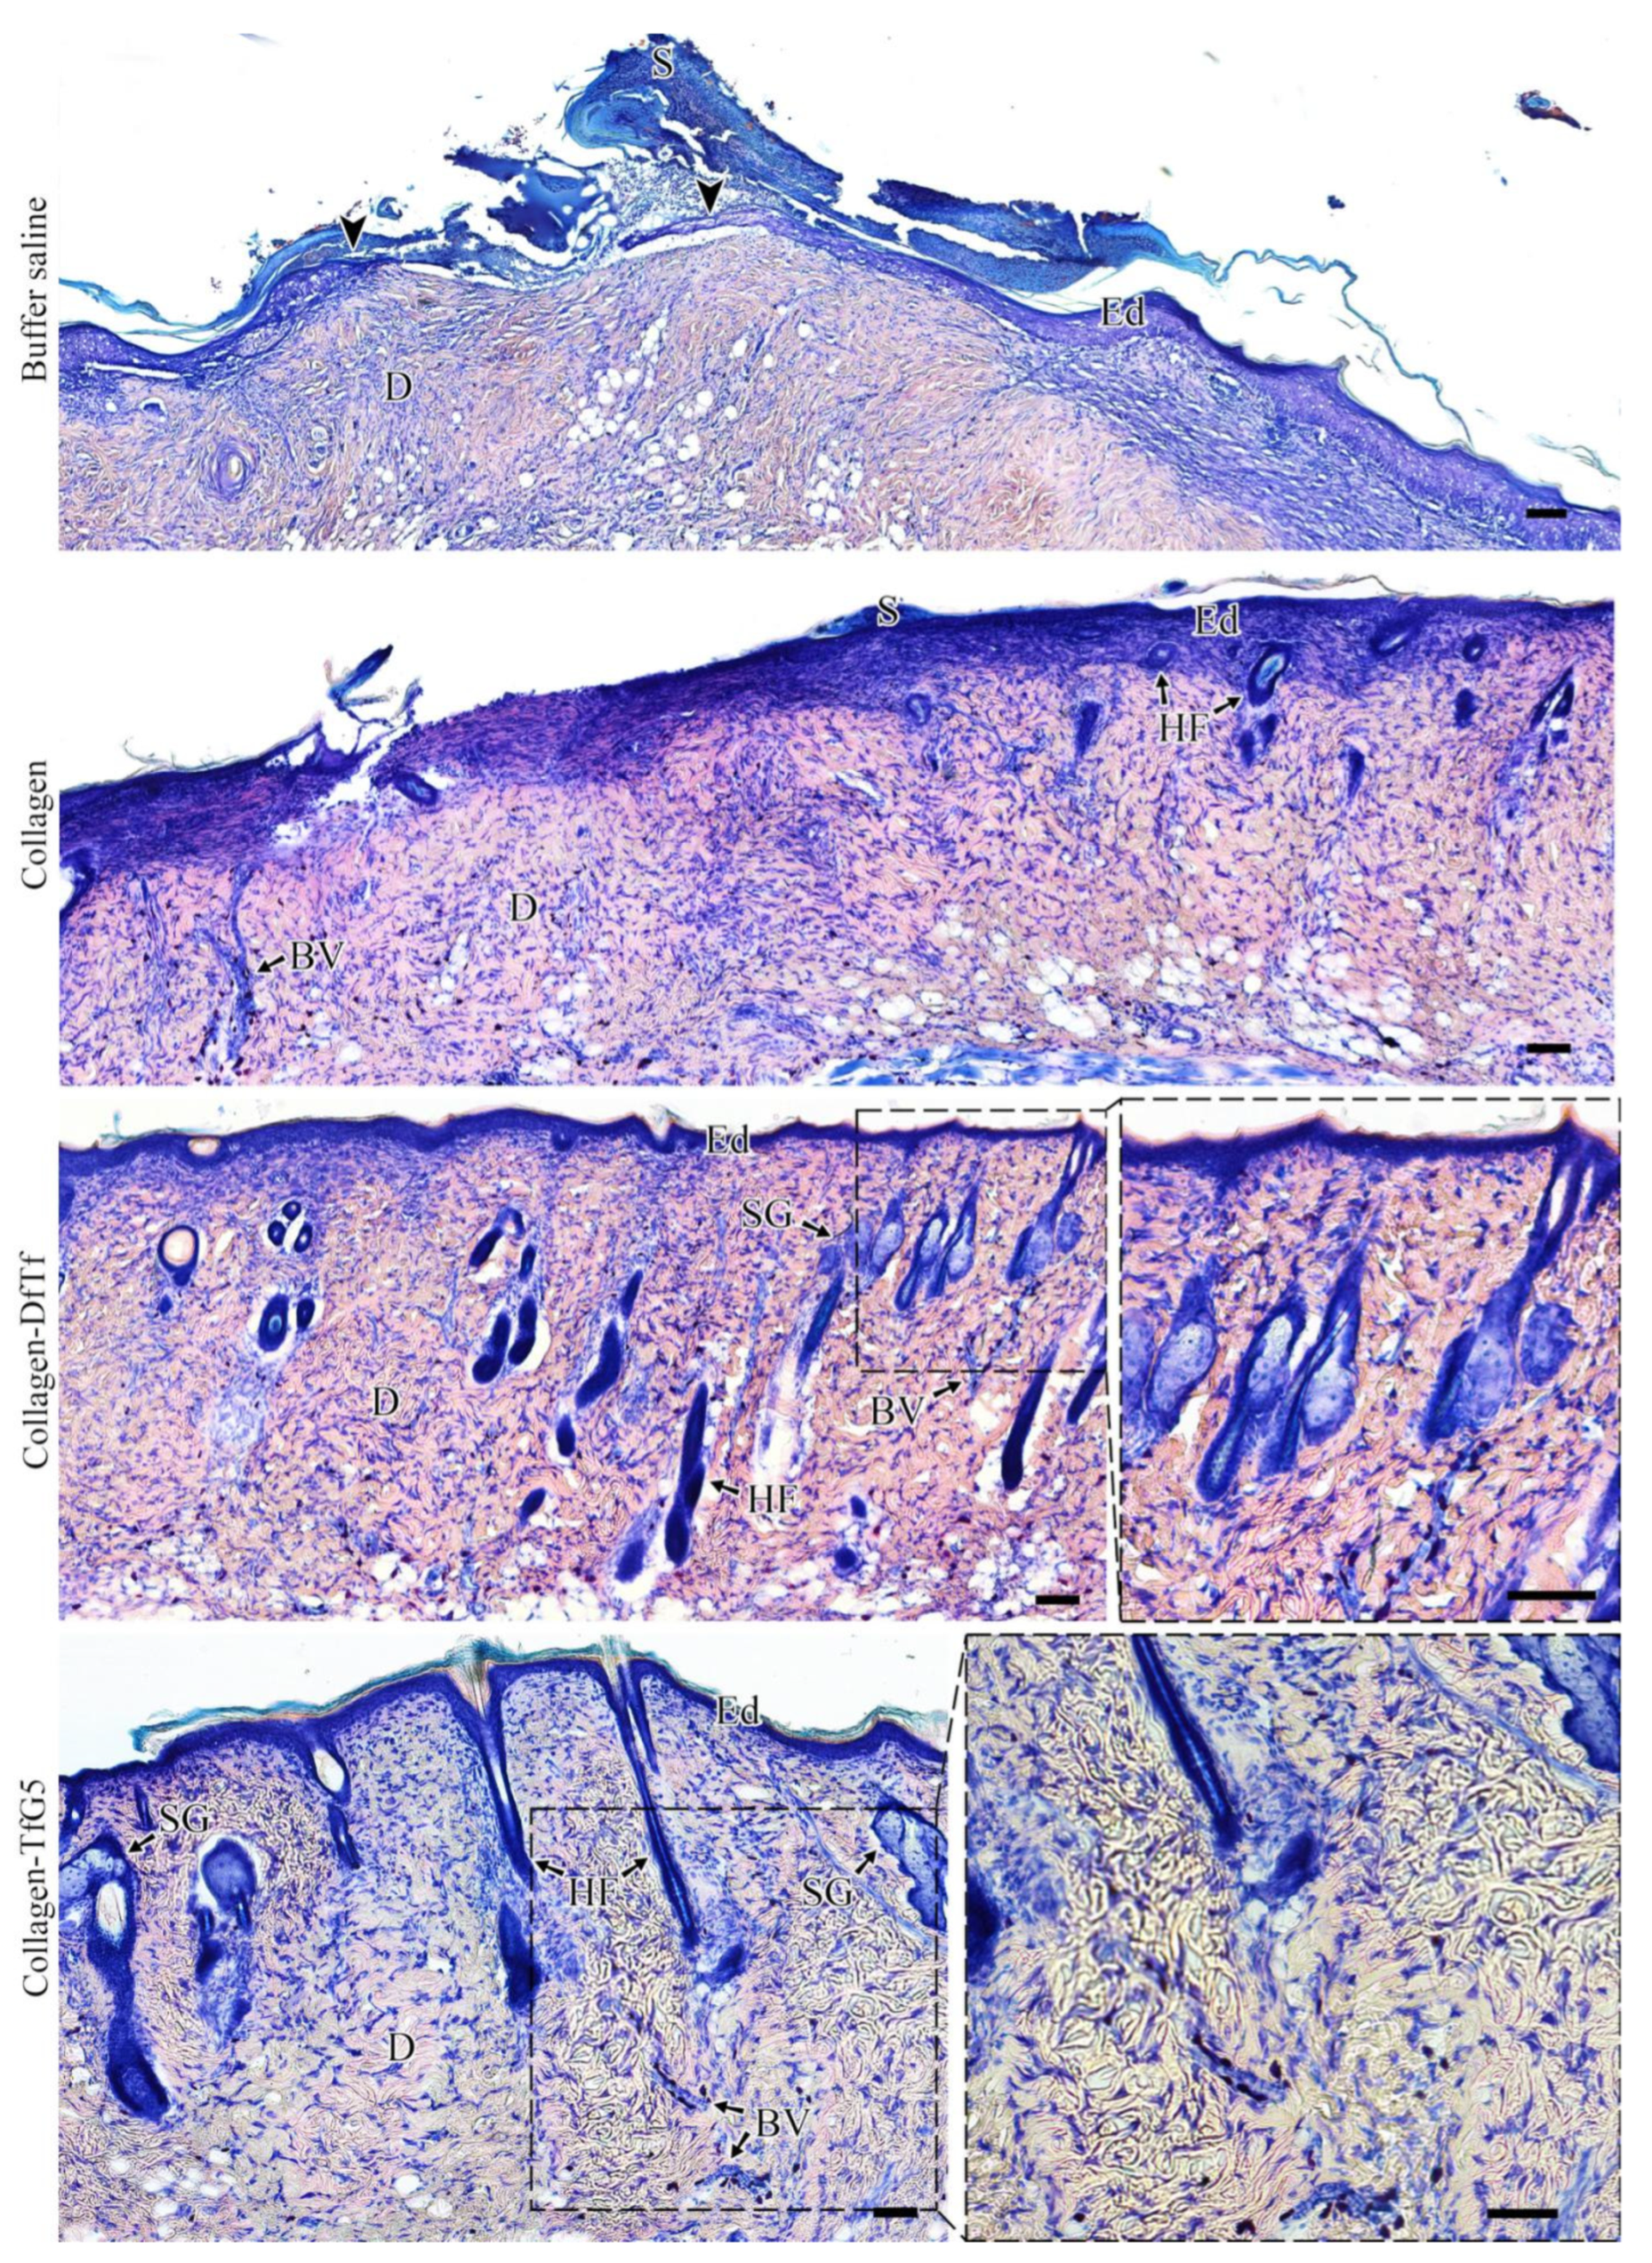

2.5. Histological Examination